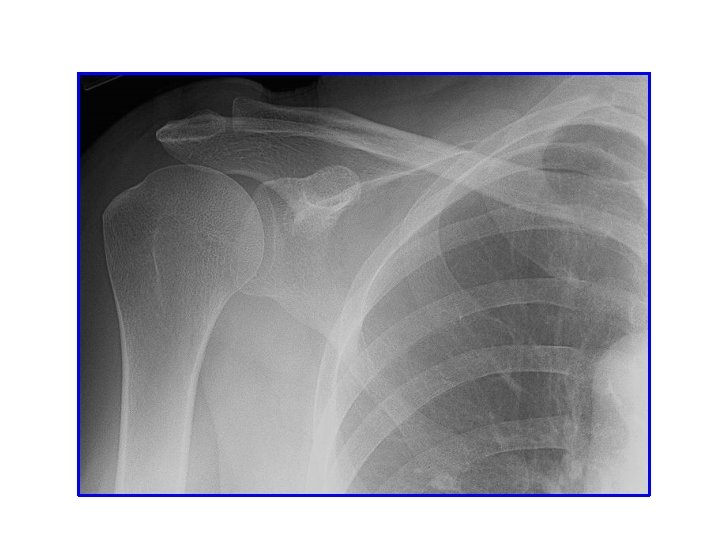

SHOULDER

X-RAY

acromion Clavicale Greater teberosity coracoid Lesser teberosity scapula glenoid